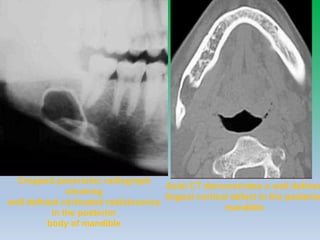

Mixed lytic and sclerotic ill defined

lesion in the body of mandible with

cortical destruction and spicualted

periosteal reaction

Bone window and soft tissue window CT of

mandible showing lucent lesion in body of

mandible with cortical destruction and

periosteal reaction- osteomyelitis